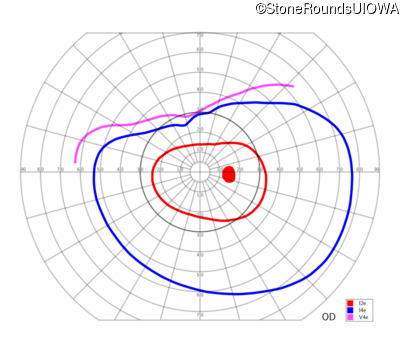

| Age at visit: 6 years |

| Age at visit: 11 years |

| Age at visit: 14 years |

| OD | OS | ||

| Age at visit: 14 years (Visit 2) |

| OD | OS | ||